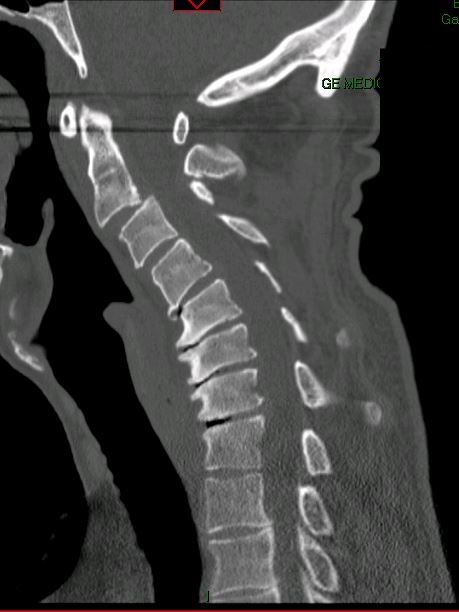

De-identified imaging from complex spine surgery cases. Each pair shows pre-operative pathology alongside post-operative correction across cervical, lumbar and deformity subspecialties.